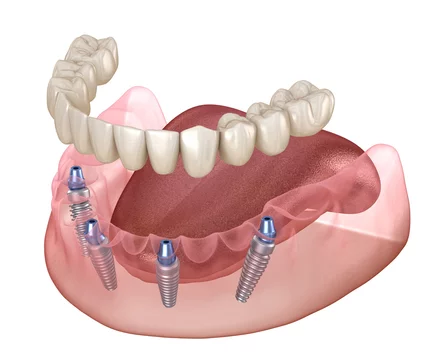

Read MoreEndosteal vs. Subperiosteal Dental Implants: Which One is Right for You?

Endosteal vs Subperiosteal: Dental implants for seniors have become a popular choice for tooth replacement, especially among seniors. However, not all dental implants are the same. In this article, we will discuss the two main types of dental implants endosteal and subperiosteal and help you determine which one is right for your unique dental situation. … Endosteal vs. Subperiosteal Dental Implants: Which One is Right for You?

Are you tired of hiding your smile due to missing teeth? Worry no more! Affordable dentures and implants are here to restore your confidence and transform your life without emptying your wallet. In this article, we’ll explore cost-effective options for dentures and implants, their benefits, and what to expect during the process. Dentures and dental implants are two popular solutions … Affordable Dentures and Implants: Your Guide to a Beautiful Smile on a Budget

As we age, our dental health becomes increasingly important, and missing teeth can significantly impact our quality of life. Dental Implants have become a popular and effective solution for seniors looking to regain their confidence and restore their smile. In this comprehensive guide, we will explore the benefits of dental implants for seniors, the types of implants available, … Dental Implants for Seniors: A Comprehensive Guide